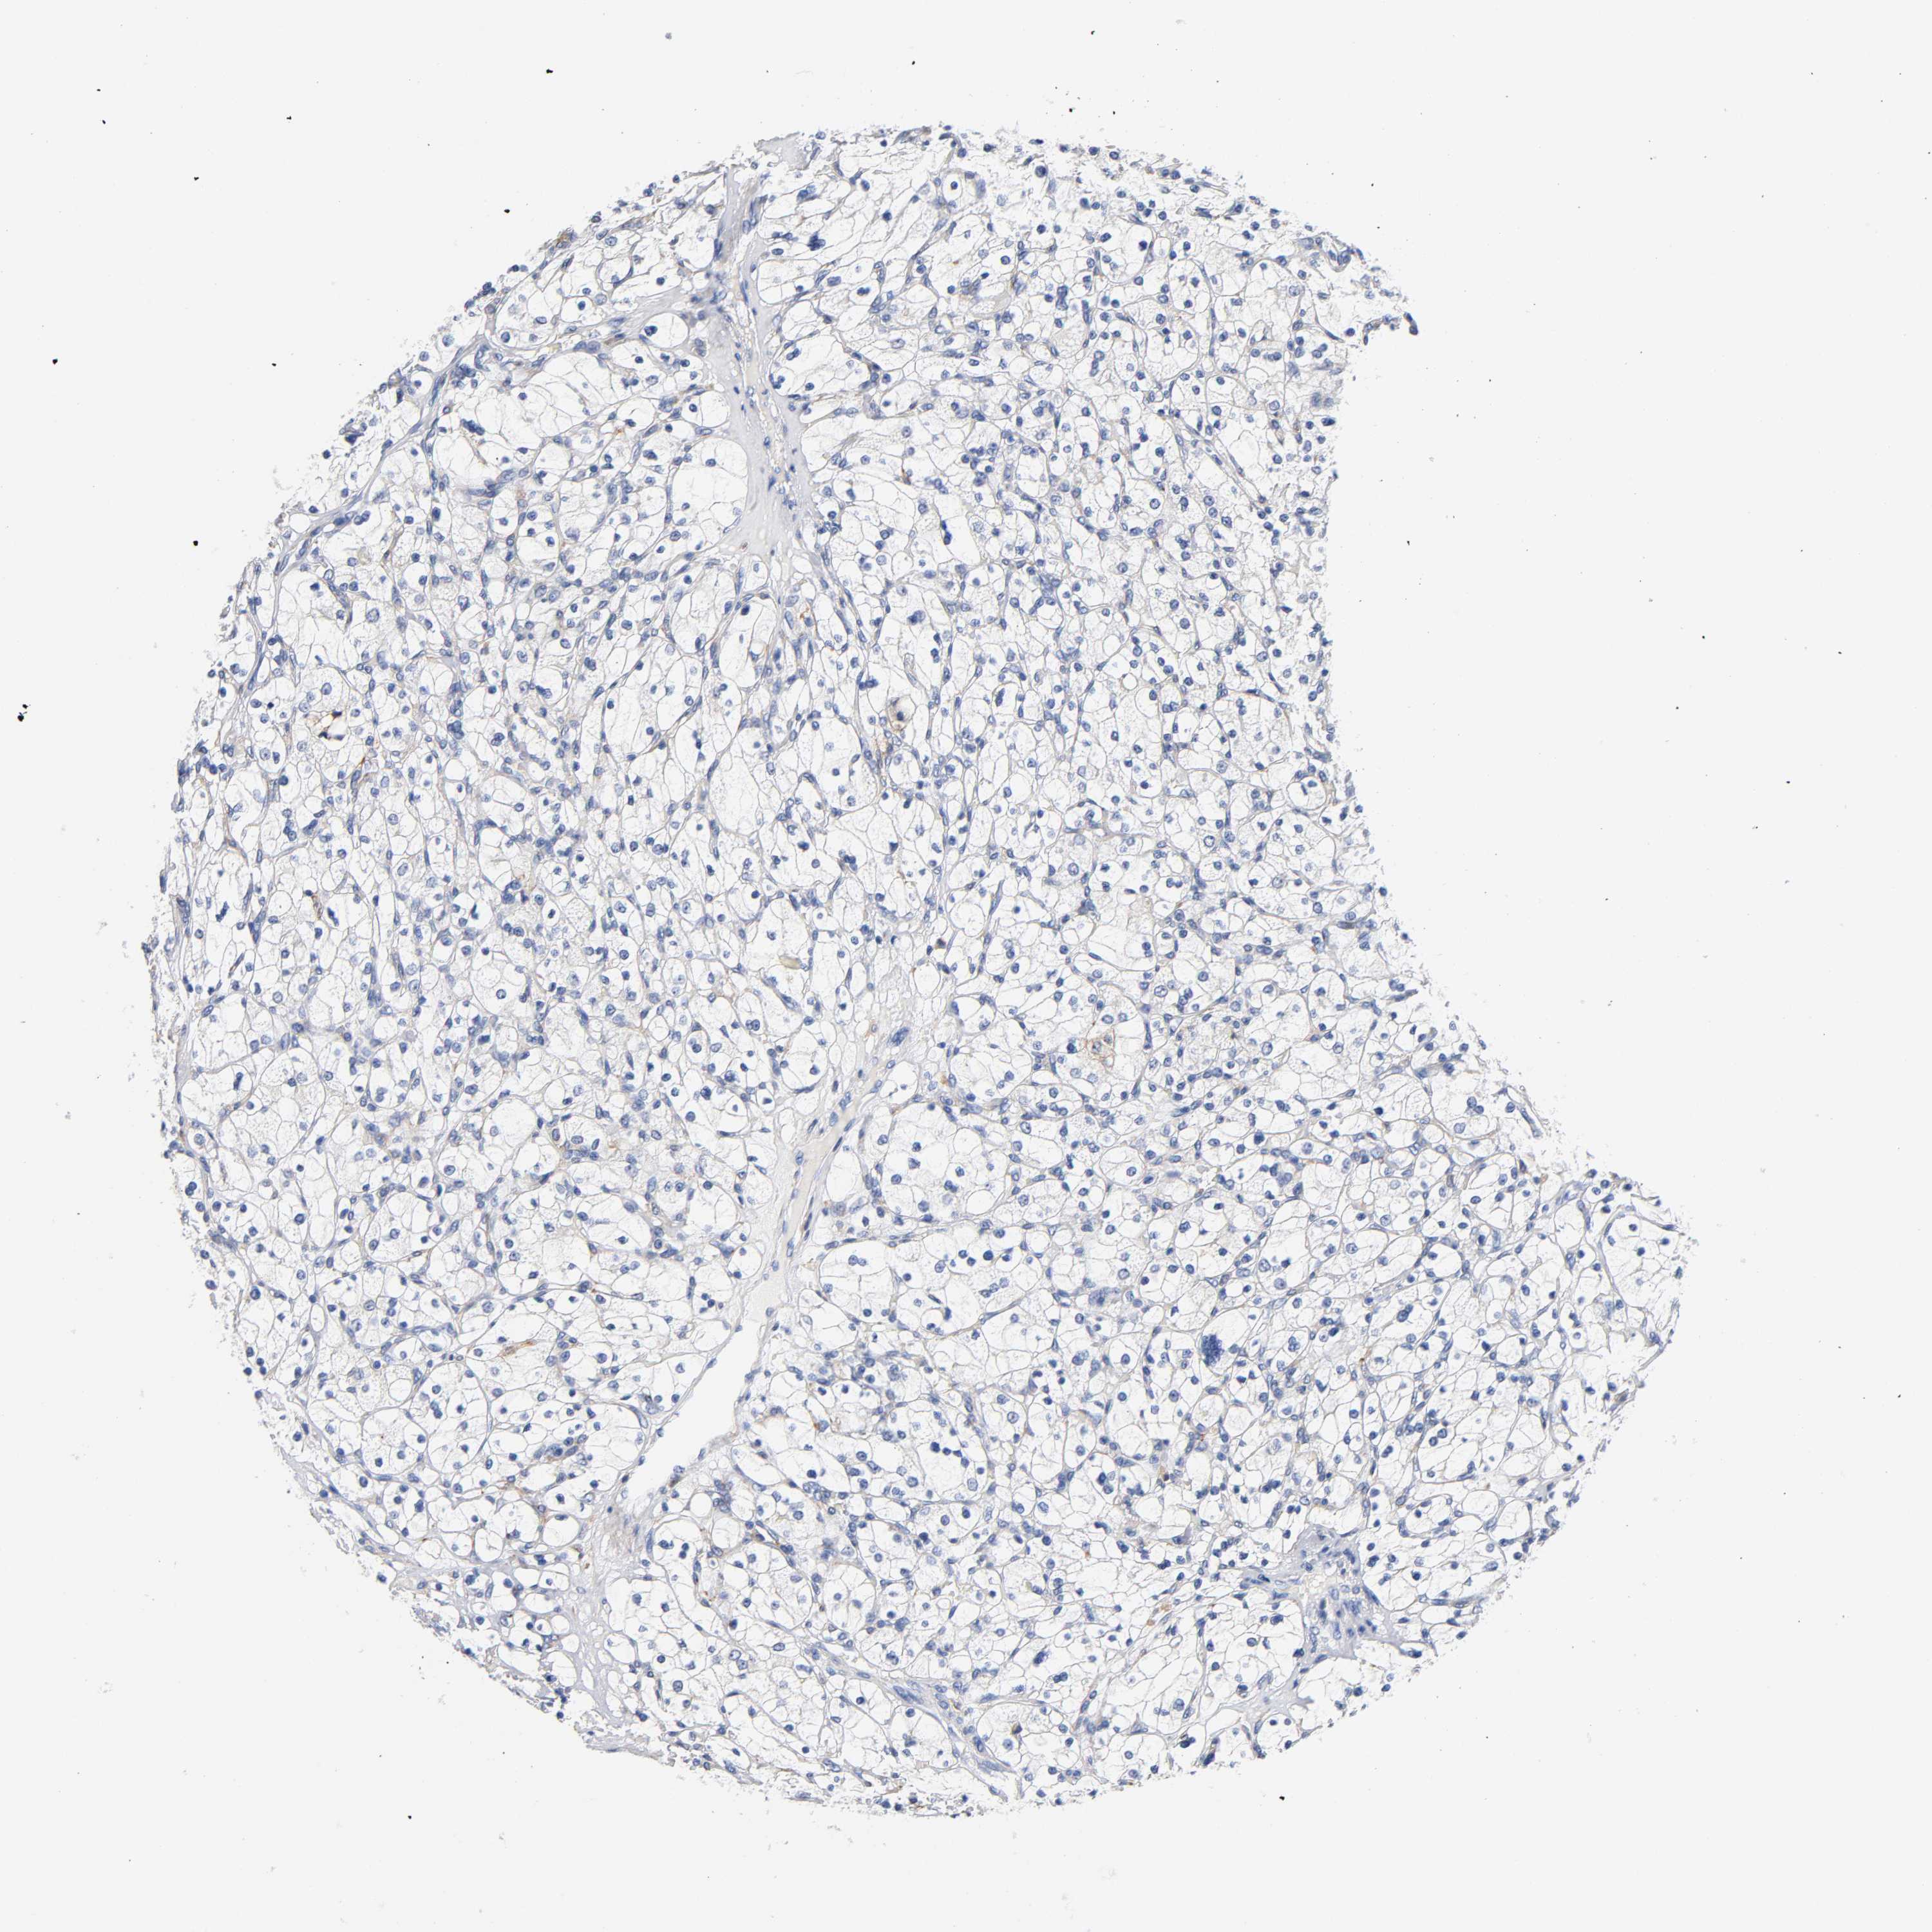

Renal cancer

Kidney chromophobe

KIDNEY CHROMOPHOBE (TCGA) - Interactive survival scatter ploti

LRP1 is not prognostic in Kidney Chromophobe (TCGA)